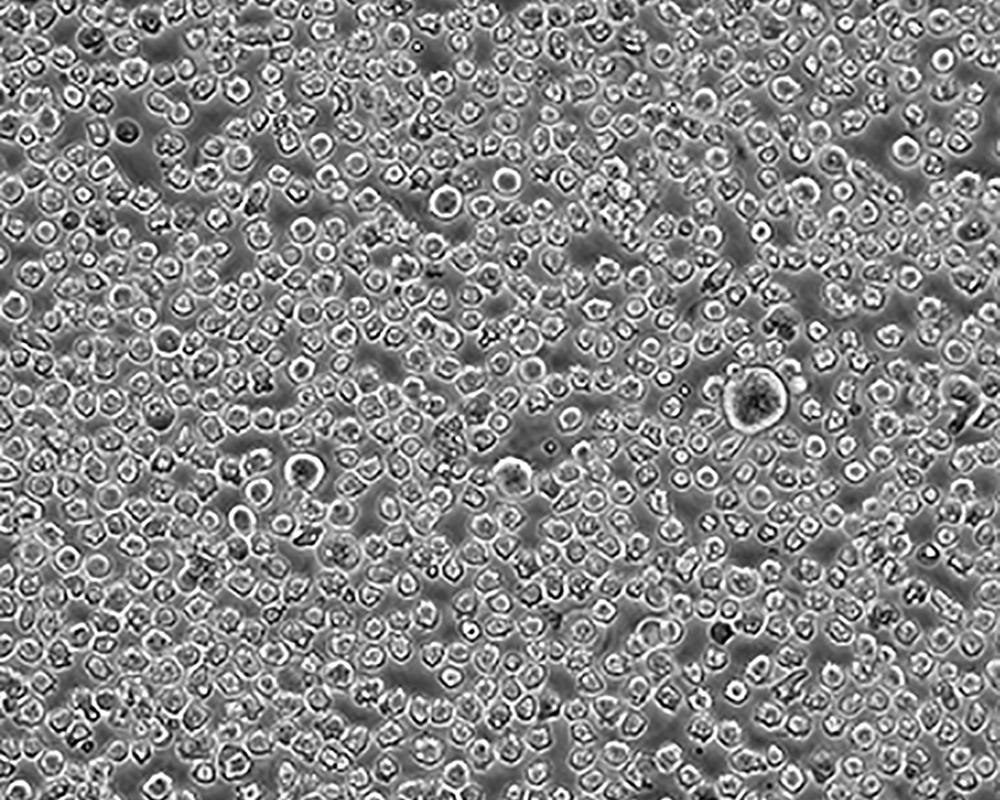

生長(zhǎng)特性 suspension

形態(tài)特征 lymphoblast

細(xì)胞描述 The cell population has been characterized as highly undifferentiated and of the granulocytic series. Studies conducted by Anderson, et al. , on the surface membrane properties led to the conclusion that the K-562 was a human erythroleukemia line. K-562 blasts are multipotential, hematopoietic malignant cells that spontaneously differentiate into recognizable progenitors of the erythrocytic, granulocytic and monocytic series. The effect of inducers on sublines derived from the original K-562 cell line have been reviewed by Koeffler and Golde. Karyological studies on various K- 562 sublines have been classified into three groups(A,B,C) by Dimery, et al. The strain obtained by the ATCC most closely resembles the B population. Occurrence of the Philadelphia chromosome, however, was of much lower frequency; none detected in 15 metaphases examined. The line is EBNA negative.